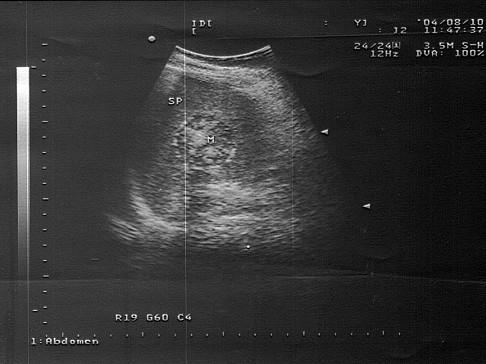

女,36岁,有乳腺癌手术史。结合超声声像图,诊断为?(?)A.脾转移性癌B.脾结核C.脾错构瘤D.脾外伤性血肿E.脾血管瘤

问题 女,36岁,有乳腺癌手术史。结合超声声像图,诊断为?(?)

选项 A.脾转移性癌 B.脾结核 C.脾错构瘤 D.脾外伤性血肿 E.脾血管瘤

答案 A